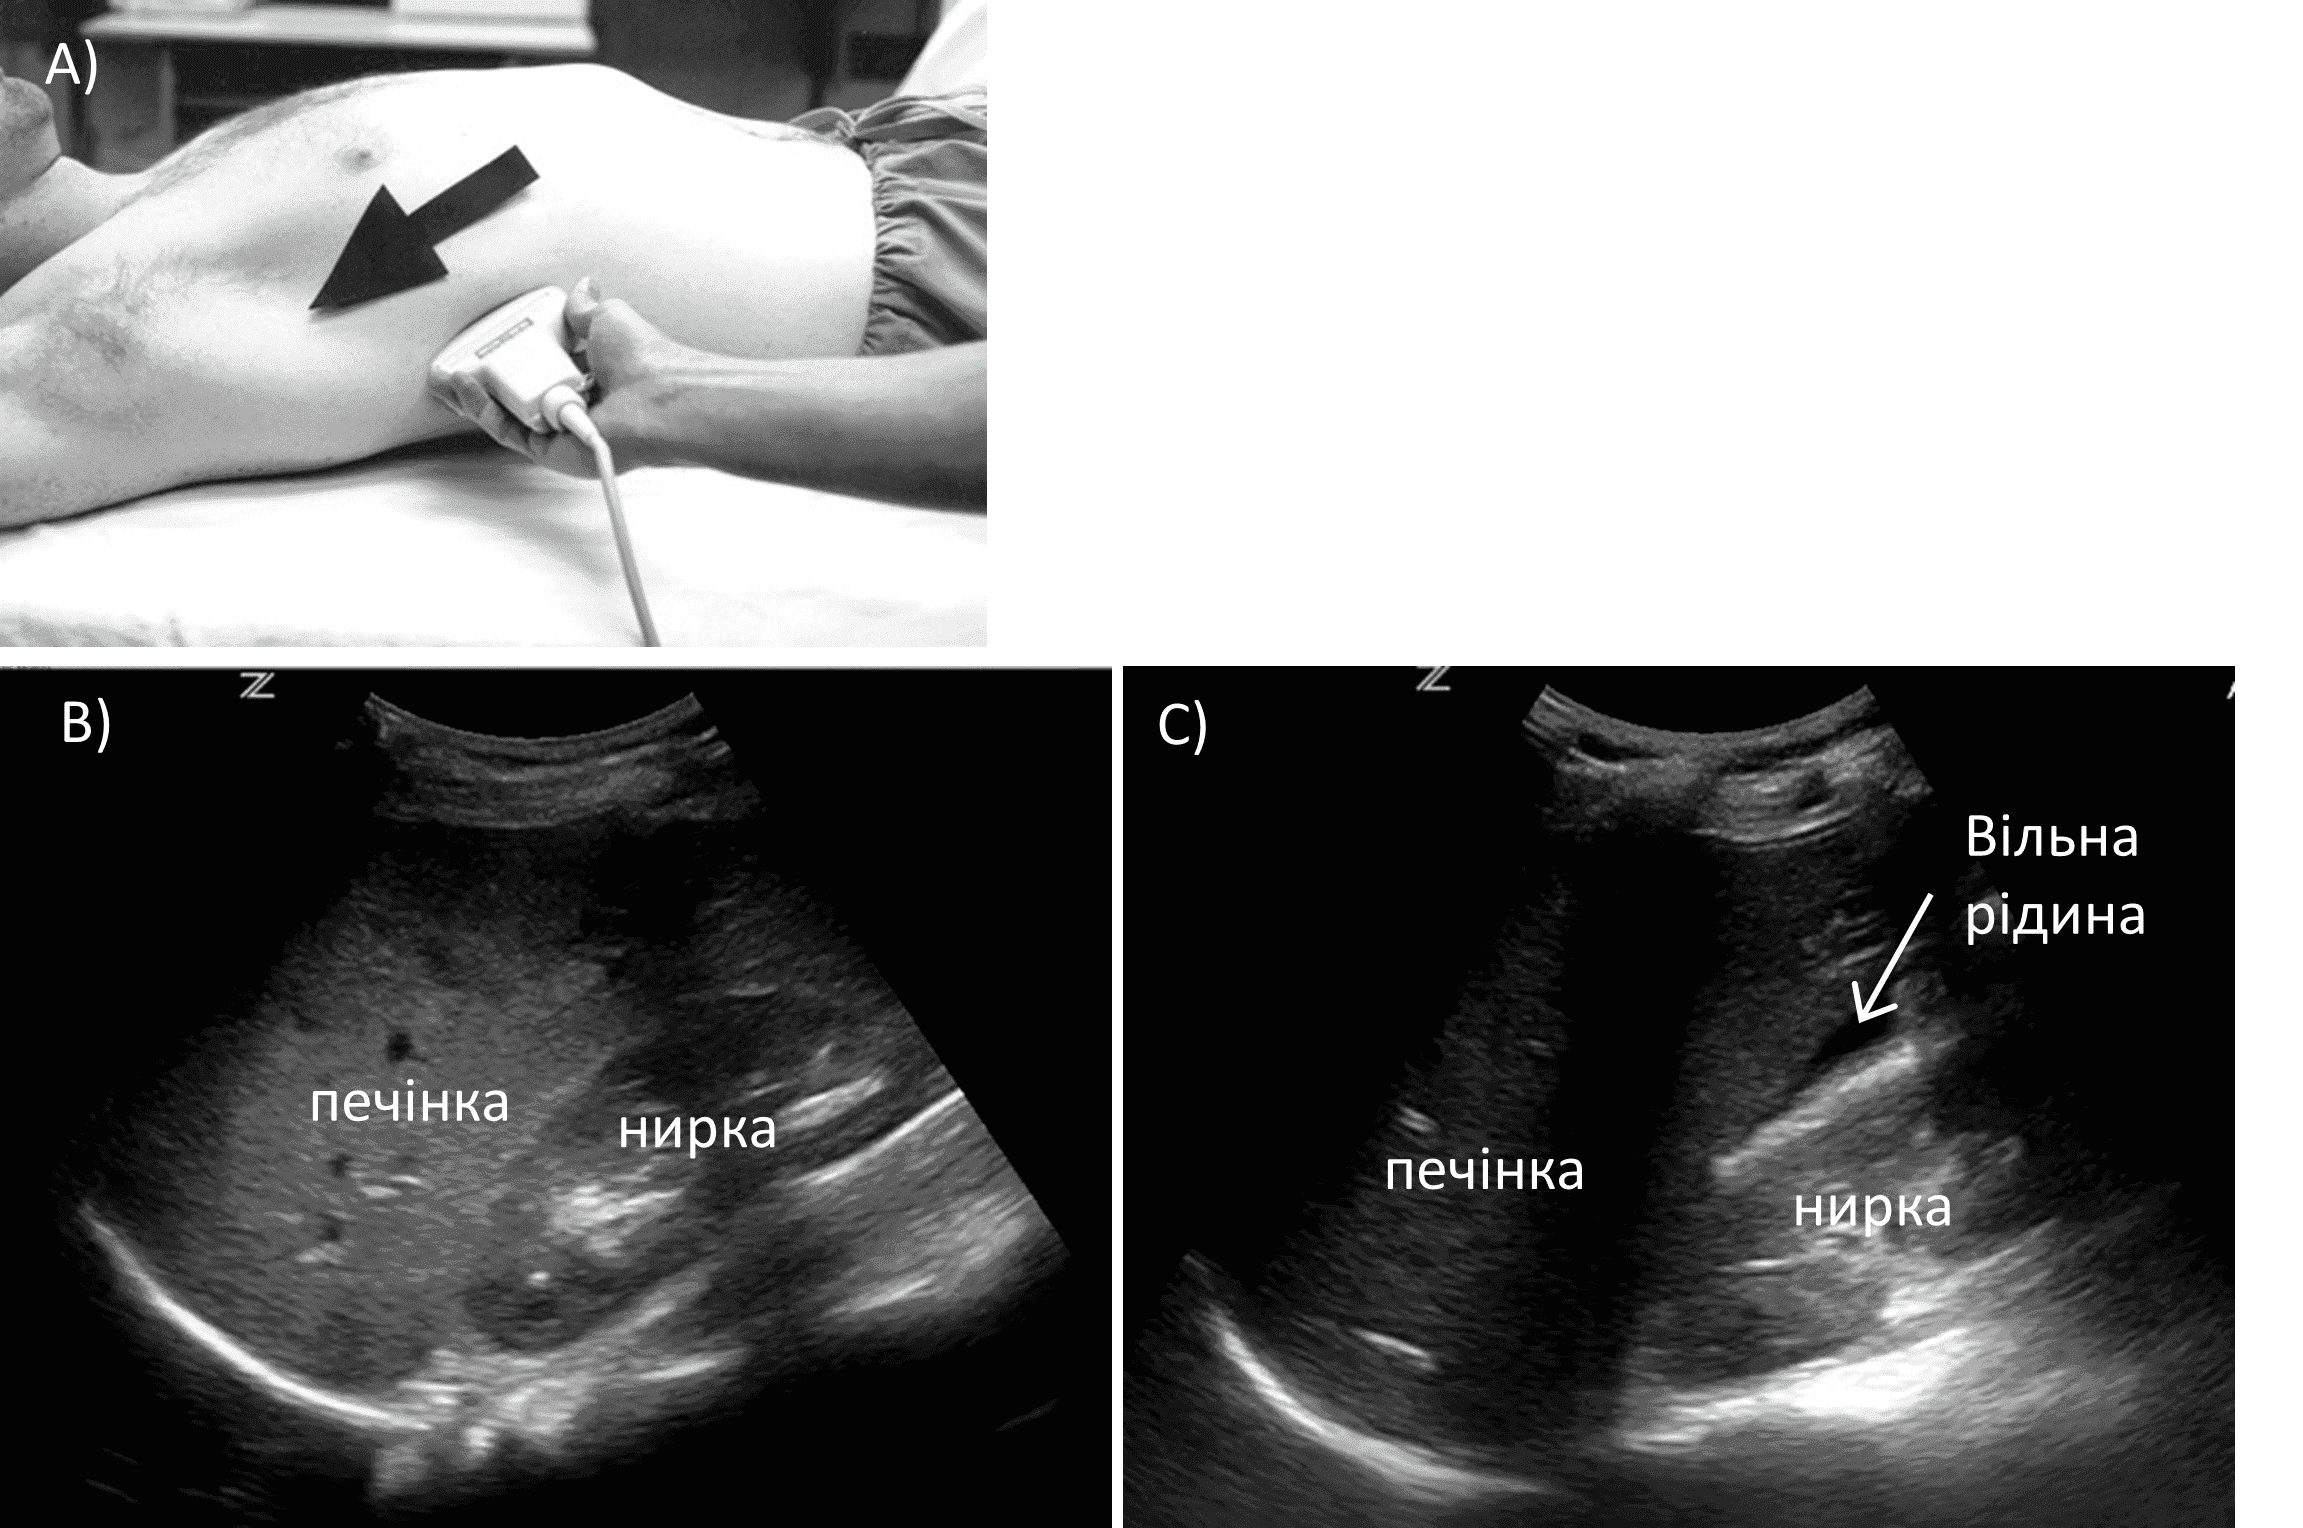

Проекцію з правого фланку отримують, розташувавши датчик між середньоключичною та задньою пахвовими лініями у 10-му або 11-му міжребер’ї так, щоб маркер зонда був спрямований до голови пацієнта (зобр. 5).

Зобр. 5. Проекція правого фланку.

A) Позиціонування датчика. B) Норма. C) Вільна рідина.

Мета полягає в тому, щоб візуалізувати край печінки, гепаторенальне заглиблення (кишеня Морісона) і гепатодіафрагмальний простір. Оскільки немає двох людей з однаковою анатомією, точне початкове розміщення датчика є менш важливим, ніж наступна корекція положення на основі отриманого зображення. Наш підхід полягає в тому, щоб спробувати ідентифікувати нирку за допомогою датчика. Якщо ж ми не можемо візуалізувати нирку, але візуалізуємо печінку, ми знаємо, що потрібно рухатися вниз. Потім датчик рухають віялоподібно, щоб послідовно оцінити кишеню Морісона та межу між ниркою та печінкою.

Іноді зображення в цій проекції може бути важко отримати через затінення ребер. Затінення ребер можна звести до мінімуму, зміщуючи зонд вгору або вниз по ребрах або обертаючи зонд проти годинникової стрілки, щоб розташувати його більш паралельно ребрам. Як не парадоксально, часто розташування зонда безпосередньо на ребрі, з подальшою незначною корекцією положення, щоб «оглянути» ребро, може бути ефективною технікою для забезпечення чіткого огляду без тіні.